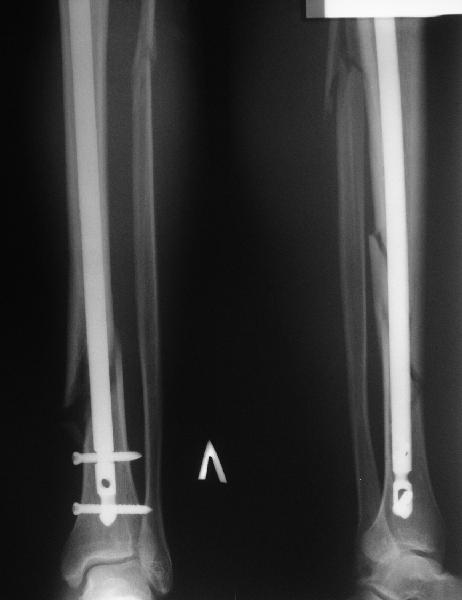

Добрый день, уважаемые коллеги. На консультацию обратился мужчина 30

лет. Месяц назад по месту жительства ему был выполнен закрытый

интрамедуллярный остеосинтез большеберцовой кости по поводу

спирального перелома обеих костей голени. Ходит с ограниченной

нагрузкой на ногу. Направлен из травмпункта по поводу оставшегося

смещения отломков. У нас разделилось мнение коллег по вопросу  - есть

ли необходимость в закрытом интрамедуллярном реостеосинтезе с

исправлением оси или только ограничиться динамизацией гвоздя.